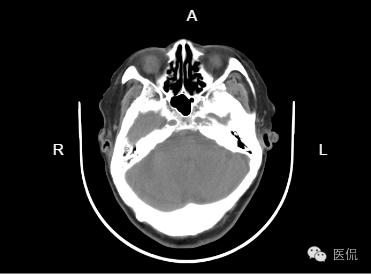

患者信息:女,80岁

检查部位:h

检查方法:平扫

患者主诉:两年前CT显示,梗塞,现正常体检

左侧基底节区及左脑干区见小斑片状低密度灶,部分边界欠清;侧脑室旁脑白质对称性减低,余双侧大脑组织内未见异常密度,脑干及小脑形态、大小正常,内未见异,中线居中,各脑室及脑池增大、脑皮层沟回加深加宽,余未见异常。骨窗下诸颅骨无明显异常。

1、左侧基底节区及左脑干腔隙性脑梗塞。建议结合临床随访复查!

2、脑白质疏松;

3、老年性脑萎缩。